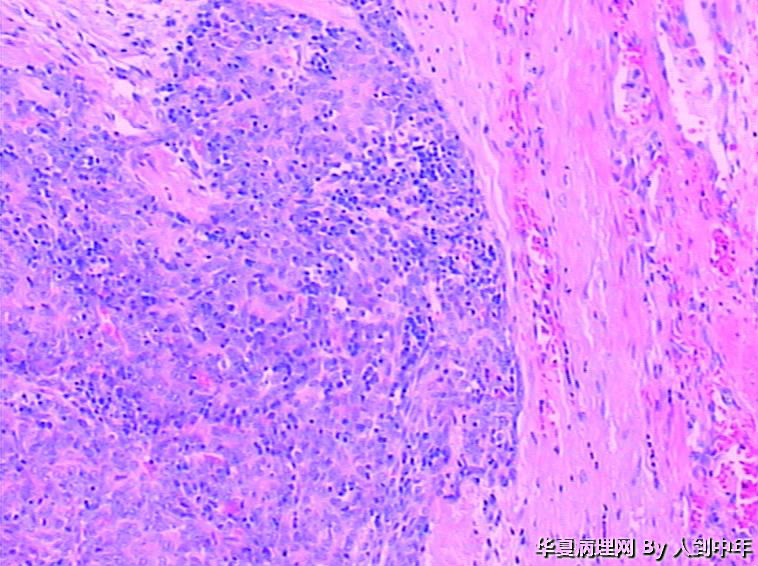

肺部肿瘤--类癌?求助大家

患者,男性,72岁,右肺中叶占位,肺门部肿物,散在多结节状,直径0.2-2.2cm。

• 肺部肿瘤--类癌?求助大家图4

图4

低分化癌,看到有腺样结构,肿瘤多结节,也要排除转移。

低分化癌,可能伴神经内分泌分化。不能标记也要建议会诊,去不去是他们的事

微囊、细胞梭形或立方、癌巢周边细胞见栅栏状(图22),不能排除基底细胞样癌。

微囊、细胞梭形或立方、癌巢周边细胞见栅栏状,不能排除基底细胞样癌。

癌,微囊、细胞梭形或立方、癌巢周边细胞见栅栏状,不能排除基底细胞样癌。多结节,也要排除转移性涎腺型恶性肿瘤,腺样囊腺癌等。